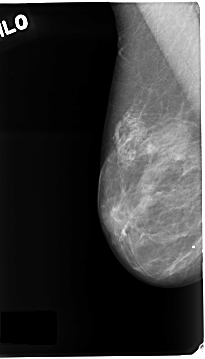

C_0123_1.RIGHT_CC

RIGHT_MLO LINES 4664 PIXELS_PER_LINE 2656 BITS_PER_PIXEL 12 RESOLUTION 50 NON_OVERLAY